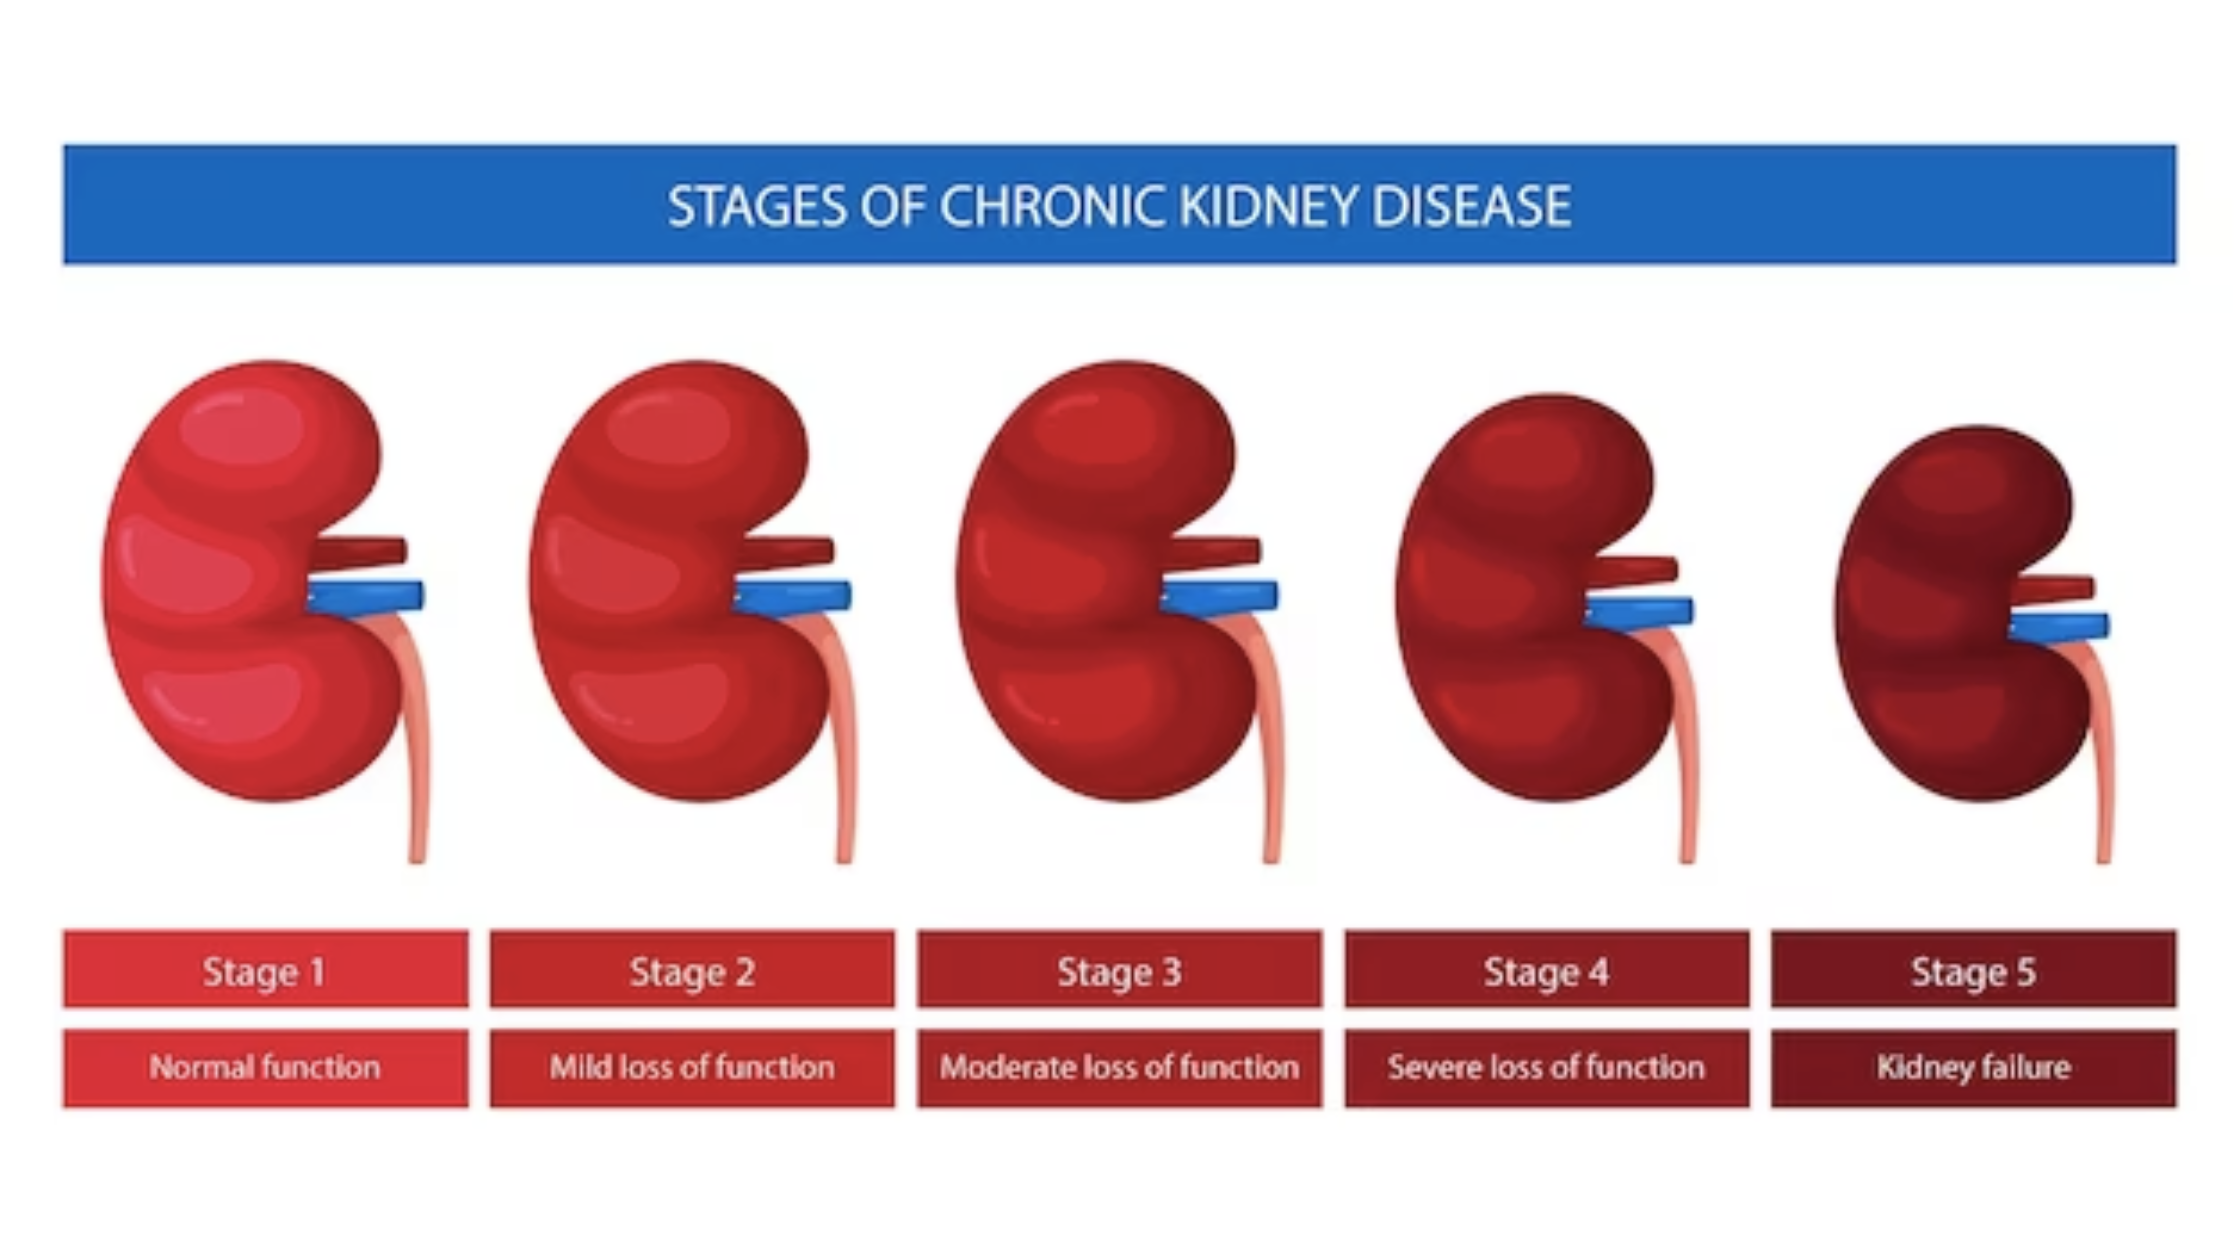

Within the complex view of human health, Chronic Kidney Disease (CKD) stands as a silent protagonist, affecting millions worldwide. As we mark its existence, what better way to delve into […]